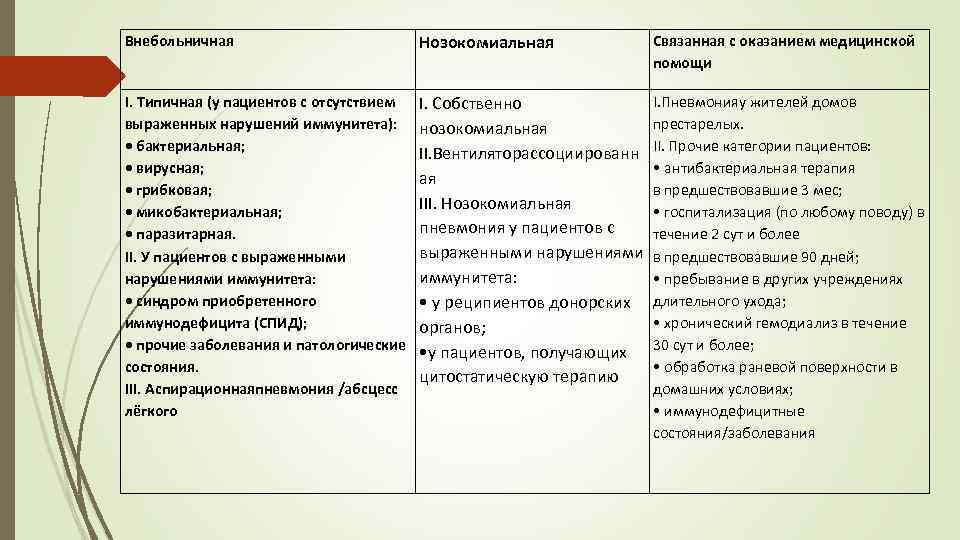

Внебольничная Нозокомиальная Связанная с оказанием медицинской помощи I. Типичная (у пациентов с отсутствием выраженных нарушений иммунитета): • бактериальная; • вирусная; • грибковая; • микобактериальная; • паразитарная. II. У пациентов с выраженными нарушениями иммунитета: • синдром приобретенного иммунодефицита (СПИД); • прочие заболевания и патологические состояния. III. Аспирационнаяпневмония /абсцесс лёгкого I. Пневмонияу жителей домов I. Собственно престарелых. нозокомиальная II. Вентиляторассоциированн II. Прочие категории пациентов: • антибактериальная терапия ая в предшествовавшие 3 мес; III. Нозокомиальная • госпитализация (по любому поводу) в пневмония у пациентов с течение 2 сут и более выраженными нарушениями в предшествовавшие 90 дней; иммунитета: • пребывание в других учреждениях • у реципиентов донорских длительного ухода; • хронический гемодиализ в течение органов; • у пациентов, получающих 30 сут и более; • обработка раневой поверхности в цитостатическую терапию домашних условиях; • иммунодефицитные состояния/заболевания

Внебольничная Нозокомиальная Связанная с оказанием медицинской помощи I. Типичная (у пациентов с отсутствием выраженных нарушений иммунитета): • бактериальная; • вирусная; • грибковая; • микобактериальная; • паразитарная. II. У пациентов с выраженными нарушениями иммунитета: • синдром приобретенного иммунодефицита (СПИД); • прочие заболевания и патологические состояния. III. Аспирационнаяпневмония /абсцесс лёгкого I. Пневмонияу жителей домов I. Собственно престарелых. нозокомиальная II. Вентиляторассоциированн II. Прочие категории пациентов: • антибактериальная терапия ая в предшествовавшие 3 мес; III. Нозокомиальная • госпитализация (по любому поводу) в пневмония у пациентов с течение 2 сут и более выраженными нарушениями в предшествовавшие 90 дней; иммунитета: • пребывание в других учреждениях • у реципиентов донорских длительного ухода; • хронический гемодиализ в течение органов; • у пациентов, получающих 30 сут и более; • обработка раневой поверхности в цитостатическую терапию домашних условиях; • иммунодефицитные состояния/заболевания